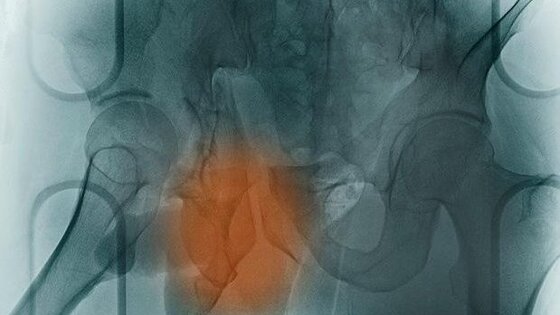

Британские ученые испытывают новую методику лечения остеопороза с помощью стволовых клеток, которые становятся новыми костями. Для этого используется специфическая вибрация. До сегодняшнего дня единственным выбором для пациентов с остеопорозом, столкнувшихся со сложными переломами, является очень болезненная хирургическая операция. Во время нее врачи удаляют кости из здоровой части тела и трансплантируют их на поврежденную зону. Однако британские исследователи установили, что стволовые клетки могут превращаться в клетки костей (остеобласты) при помощи вибраций низкой интенсивности. Стволовые клетки уже давно считаются будущим медицины, поскольку они обладают способностью трансформироваться в любые клетки организма в зависимости от потребностей. Исследователи из Университета Восточной Шотландии и Университета Глазго полагают, что вибрации при частоте в 1000Hz повторяют условия, с которыми сталкивается натуральная кость в организме. А это побуждает стволовые клетки превращаться в кости в течение 28 дней, чтобы потом быть имплантированными. Авторы методики надеются, что та же самая частота вибрации может быть использована для стимуляции заживления внутри тела даже без трансплантаций. Они подчеркивают, что подобного рода вибрации организм человека испытывает постоянно от различных механических стимуляций вроде ходьбы пешком или сердцебиений. Данная методика использует механоэлектрические свойства костей, конвертирующих механический стресс в электричество, что и происходит при частоте в 1000Hz. Доказано, что кости сохраняют свое здоровье только при активных нагрузках, и поэтому космонавты достаточно быстро теряют костную массу в условиях гравитации. Именно поэтому для трансформирования стволовых клеток в кости используется техника вибрации. (ЧИТАТЬ ДАЛЕЕ)